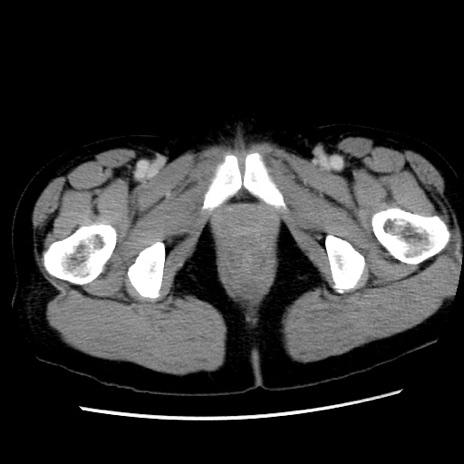

冠状断像